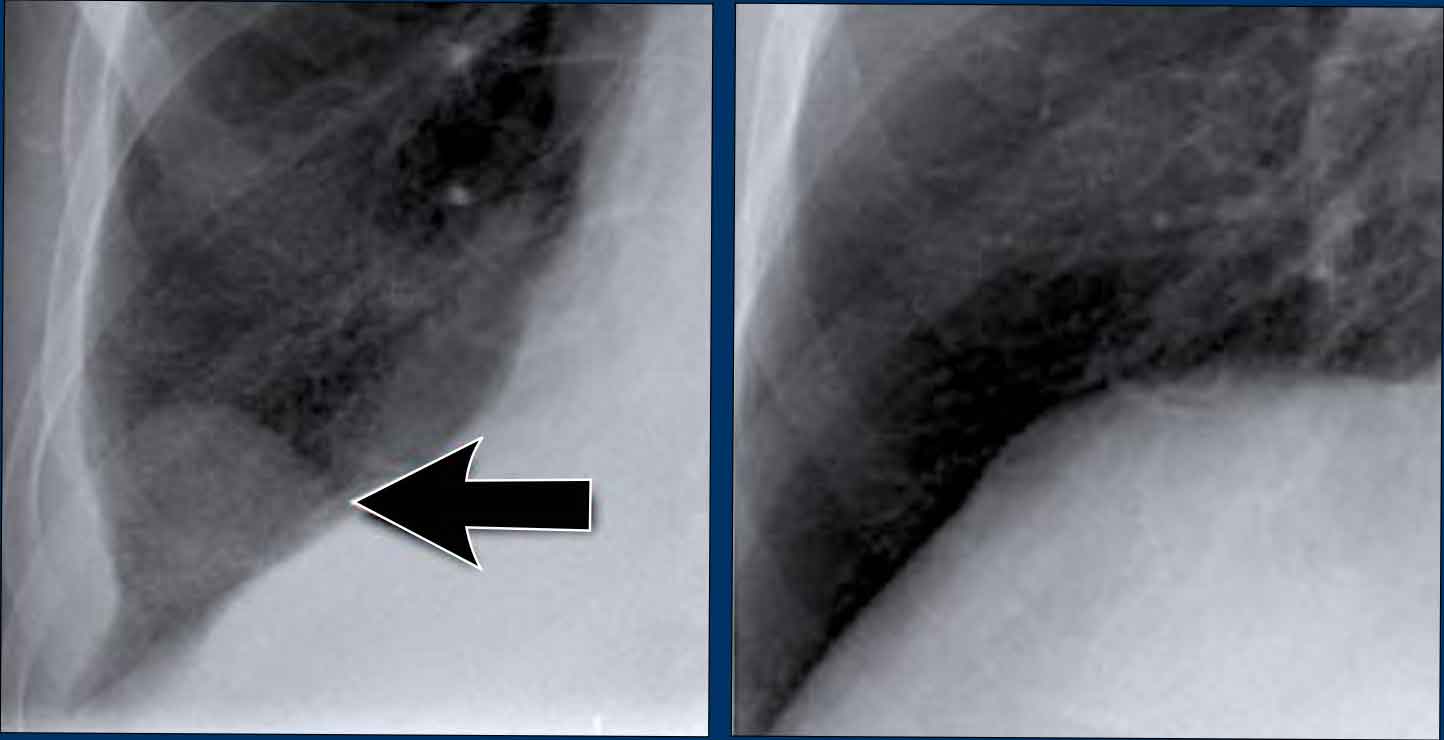

Case Example: Subtle Signs of Congestive Heart Failure

Begin by reviewing these current chest radiographs.

Based solely on these images, one might suspect congestive heart failure (CHF), though the findings are subtle.

Now review the previous study…

Scrolling between the current and prior films significantly increases diagnostic confidence in your diagnosis of congestive heart failure.

Key comparative findings include:

• Cardiac size: Slightly increased compared to the previous study; however, cardiomegaly was already present.

• Pulmonary vasculature: Mild vascular engorgement suggesting elevated pulmonary venous pressure.

• Interstitial markings: Subtle signs of interstitial edema .

• Pleural effusions: Bilateral small effusions, with subtle changes in the inferoposterior borders of the lower lobes, suggesting fluid accumulation.